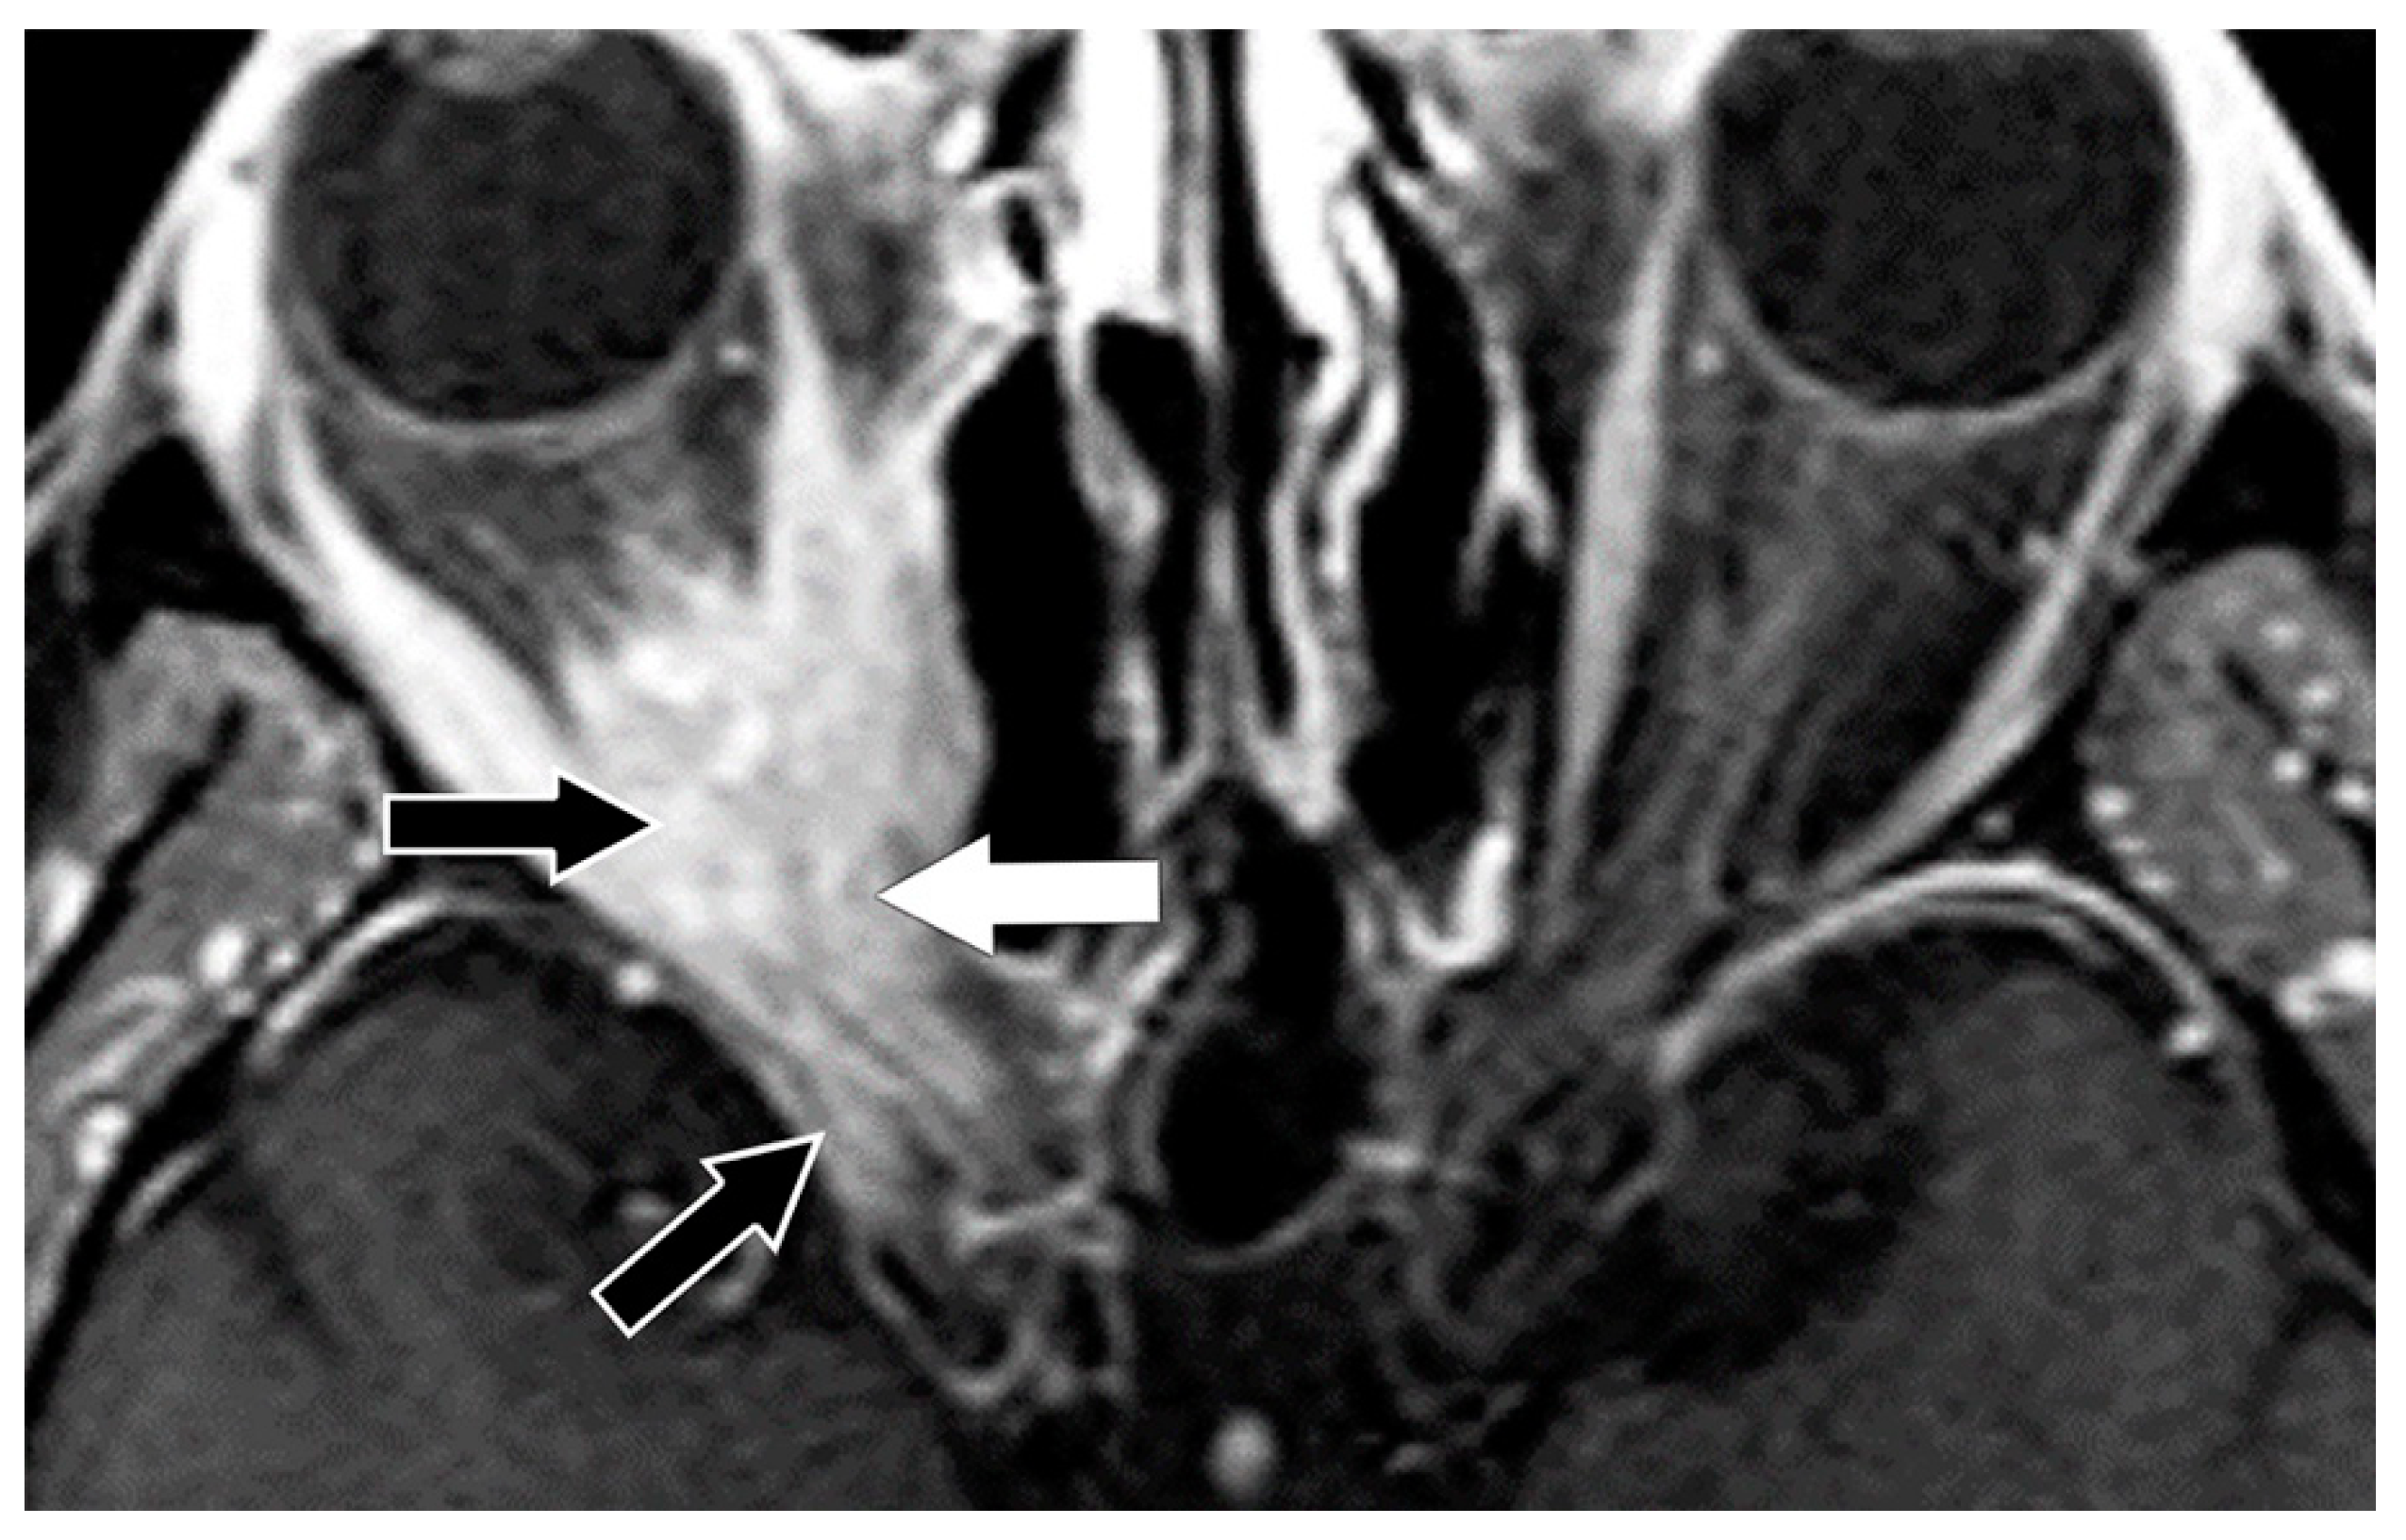

From www.mdpi.com

Biomedicines Free FullText Graves’ Eye Disease Clinical and Graves Disease Tachycardia graves' disease is an autoimmune disease which primarily affects the thyroid gland. Graves’ disease is an autoimmune disease in which your immune system attacks healthy tissue in your. it has long been recognized that some of the most characteristic and common signs and symptoms of thyroid disease are those that. It may also affect multiple other organs including.. Graves Disease Tachycardia.